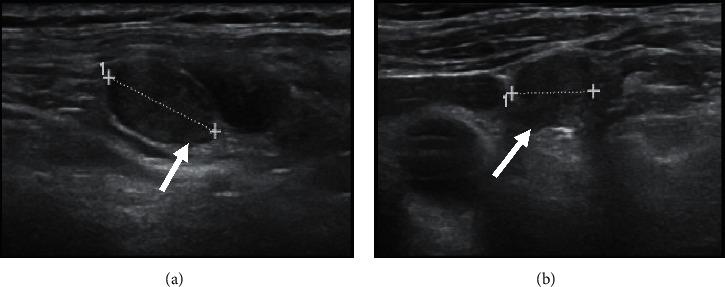

Over 50% of patients with papillary thyroid carcinoma (PTC) have cervical lymph-node metastasis on diagnosis, and up to 30% show nodal recurrence after surgery plus radioactive iodine (131I) (RAI) therapy. The combination of ultrasonography (US) and fine-needle aspiration cytology (FNAC) and the measurement of thyroglobulin (Tg) in washout fluid are cornerstones in the diagnosis of nodal metastasis. In the absence of anti-Tg antibodies, unstimulated serum thyroglobulin (Tg) levels are generally a reliable marker of recurrent disease, and 18F-FDG positron emission tomography (PET)/computed tomography (CT) plays an important role in the imaging work-up. We report the case of a 65-year-old man evaluated for a large multinodular goitre which caused compressive symptoms; the dominant nodule in the left lobe presented suspicious features on US. Thyroid function showed subclinical hypothyroidism, calcitonin was normal, serum thyroglobulin levels were low, and anti-thyroid antibodies were absent. The prevalent left nodule showed an intense uptake on 18F-FDG PET/CT but proved benign at FNAC. On the basis of the suspicious clinical and imaging features, total thyroidectomy was performed. Histology revealed a tall-cell variant of PTC with scattered expression of Tg and diffuse high expression of cytokeratin (CK) 19; RAI therapy was performed. Within 6 years of surgery, left laterocervical lymph-node recurrence was twice detected (first at levels II and III, then at levels IV and VI) by US and 18F-FDG-PET/CT and was confirmed by FNAC. Tg levels in the washout fluid proved clearly diagnostic of metastasis only in the second, larger, recurrence, whereas serum Tg levels (in the absence of anti-Tg antibodies) always remained undetectable on L-thyroxine therapy. Surgery was performed on both recurrences, and histology confirmed lymph-node metastasis of PTC. Immunohistochemical expression of Tg and CK 19 was similar to that of the primary tumour. No further relapses have occurred to date. Posttherapy (surgery and RAI) unstimulated serum Tg levels may not be a reliable marker of nodal recurrence in patients with differentiated thyroid cancer (DTC) that produces low amounts of Tg.

超过50%的甲状腺乳头状癌(PTC)患者在诊断时已有颈部淋巴结转移,高达30%的患者在手术加放射性碘(131I)(RAI)治疗后出现淋巴结复发。超声检查(US)、细针穿刺细胞学检查(FNAC)以及冲洗液中甲状腺球蛋白(Tg)的检测相结合,是诊断淋巴结转移的基石。在不存在抗Tg抗体的情况下,未刺激血清甲状腺球蛋白(Tg)水平通常是复发疾病的可靠标志物,18F-FDG正电子发射断层扫描(PET)/计算机断层扫描(CT)在影像学检查中发挥着重要作用。我们报告了一例65岁男性患者,因巨大结节性甲状腺肿出现压迫症状而接受评估;左叶的优势结节在超声检查中呈现可疑特征。甲状腺功能显示亚临床甲状腺功能减退,降钙素正常,血清甲状腺球蛋白水平低,且无抗甲状腺抗体。优势的左侧结节在18F-FDG PET/CT上显示摄取增强,但在FNAC检查中被证明为良性。基于可疑的临床和影像学特征,进行了全甲状腺切除术。组织学检查显示为PTC的高细胞变体,Tg呈散在表达,细胞角蛋白(CK)19呈弥漫性高表达;进行了RAI治疗。在手术后6年内,通过超声检查和18F-FDG-PET/CT两次检测到左侧颈外侧淋巴结复发(首次在Ⅱ区和Ⅲ区,随后在Ⅳ区和Ⅵ区),并经FNAC证实。冲洗液中的Tg水平仅在第二次较大的复发中明确诊断为转移,而在左甲状腺素治疗期间,血清Tg水平(在不存在抗Tg抗体的情况下)始终未被检测到。对两次复发均进行了手术,组织学检查证实为PTC的淋巴结转移。Tg和CK 19的免疫组化表达与原发肿瘤相似。迄今为止未再发生复发。在分化型甲状腺癌(DTC)产生少量Tg的患者中,治疗后(手术和RAI)未刺激血清Tg水平可能不是淋巴结复发的可靠标志物。